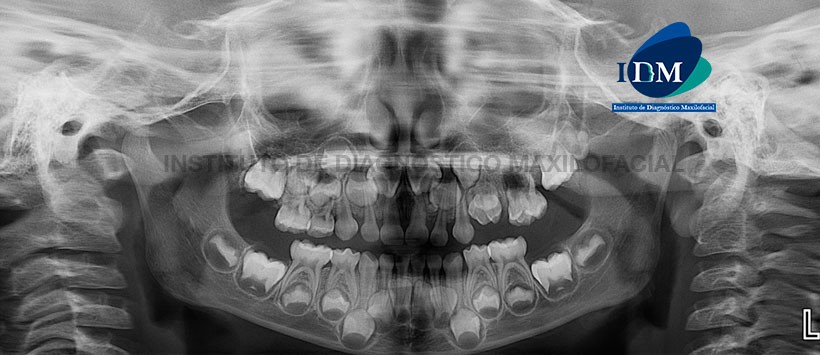

En la radiografía panorámica (Figura 1) se observa alteración en la morfología de piezas 6.4 y 6.5. A nivel de la pieza 6.5 se aprecia un proceso osteolítico periapical. No se visualizan los gérmenes dentarios de las piezas 2.4 y 2.5. También se visualiza presencia de aparentes dentículos a nivel interadicular de piezas 6.1 y 6.2 a nivel coronario del germen de la pieza 2.2

A la evaluación de la tomografía volumétrica (CBCT) cortes axiales (Figura 2), transaxiales (Figura 3, 4 y 5) y tangenciales (Figura 6), se aprecia la presencia de dentículos delimitado por un halo hipodenso localizado a nivel del borde incisal del germen dentario de pieza 2.2 y a nivel de la tabla ósea vestibular. Se evidencia la alteración morfológica de piezas 6.4 y 6.5 caracterizada por evaginación asociado a cúspide supernumeraria de pieza 6.4, invaginación en pieza 6.5 y aumento del tamaño dentario. Presencia de caries en pieza 6.5 asociado a proceso osteolítico peri-radicular con aumento de la densidad ósea circundante (osteítis condensante) (Figura 7). Como hallazgo se observa también contenido isodenso en el antro del seno maxilar izquierdo.

En las reconstrucciones 3D se observan con detalle las alteraciones morfológicas y el proceso infeccioso (Figura 8, 9 y 10).